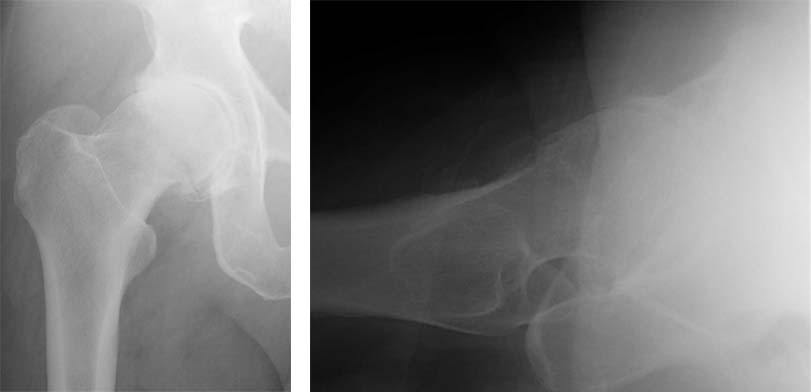

The following case is an illustration of the steps involved in a resurfacing total hip replacement performed in a 58 year old male with osteoarthritis of the right hip.

1.These radiographs show advances arthritis of the right hip. The architecture of the femoral head is consistent with femoroacetabular impingement as the underlying cause of the osteoarthritis. The patient elected to have right hip resurfacing total hip replacement.